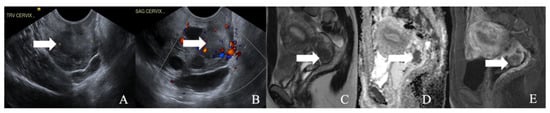

Figure 4. A 52-year-old female with a neuroendocrine tumor of the cervix uteri. (A) Transverse and (B) sagittal ultrasound image of the cervix demonstrates a heterogenous cervical mass (arrow) measuring about 14 cm. (C) Sagittal T2 weighted image, (D) sagittal apparent diffusion coefficient map, and (E) sagittal fat-saturated post-contrast T1 weighted MRI images demonstrate a mass in the cervix uteri (arrow) with restricted diffusion. The mass biopsy reported a small cell neuroendocrine tumor of grade G3.

Cancers 14 01835 g004